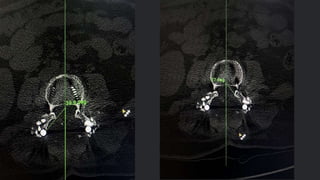

Preoperative and post operative CT SCAN is

taken

Facet angle, disc height and lateral listhesis is

noted both preoperative and postoperative

RADIOLOGICAL EVALUATION